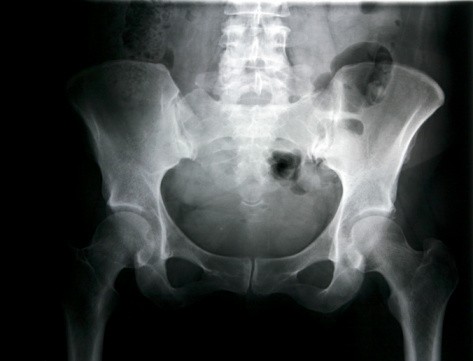

Menurut dr Ayodhia Soebadi, SpU, dari Fakultas Kedokteran Unair Surabaya, nyeri merupakan dampak paling ringan dari cedera selangkangan. "Yang berat terjadi robekan di jalan kencing atau jalan lahir atau jalan BAB," terangnya.

Karena itu, dr Arie Sutopo, SpKO, yang merupakan Ketua Bidang IPTEK KONI DKI Jakarta mewanti-wanti agar cedera selangkangan segera ditangani dengan tepat. "Dampak cedera pada selangkangan biasanya menimbulkan rasa nyeri yang hebat dan jika tidak ditangani dengan tepat dan cepat akan menjadi kronis," pesan dr Arie.